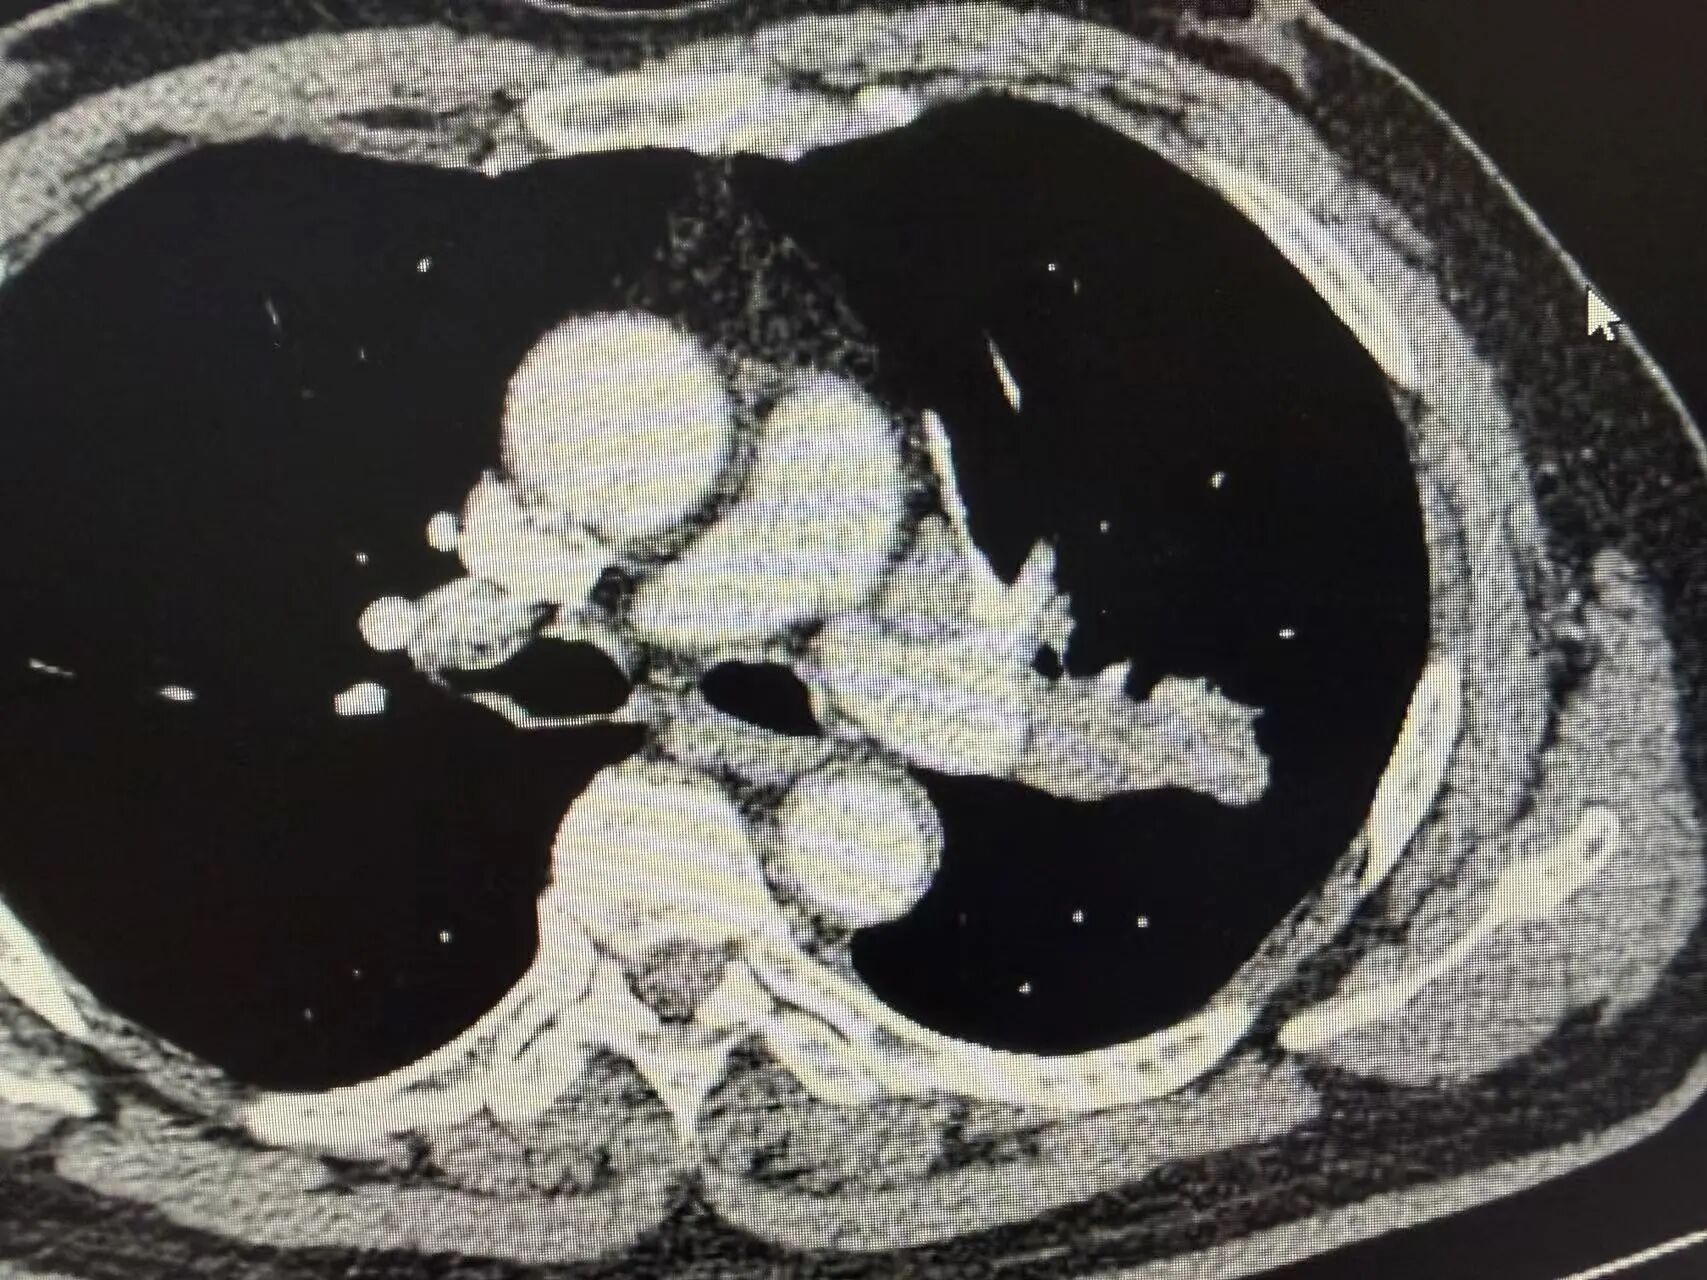

胸部增强CT结果显示:左上肺可见明显占位性病变,体积较大,同侧肺门淋巴结伴随肿大。后续穿刺病理活检明确诊断为肺鳞状细胞癌,结合淋巴结转移情况,分期为局部晚期(Ⅲa期)

新辅助治疗前CT影像